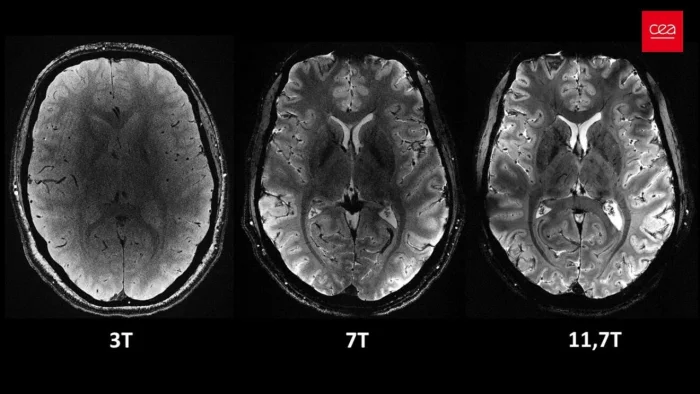

МРТ Iseult работает при максимальной магнитной мощности 11,7 Тесла (Т), что является исключительно высоким показателем по сравнению с обычными МРТ-сканерами. Обычно сканеры работают при гораздо меньших напряженностях магнитного поля, как правило, около 1,5 Т и 3 Т.

Такая высокая магнитная мощность обеспечивает лучшее качество изображения. Пространственное разрешение сканирования составляет 200 микрометров (мкм), то есть прибор может определить две точки, находящиеся на расстоянии всего 200 мкм друг от друга. Такое высокое разрешение обеспечивает более структурированные и точные изображения, что позволяет врачам более эффективно проводить исследования.